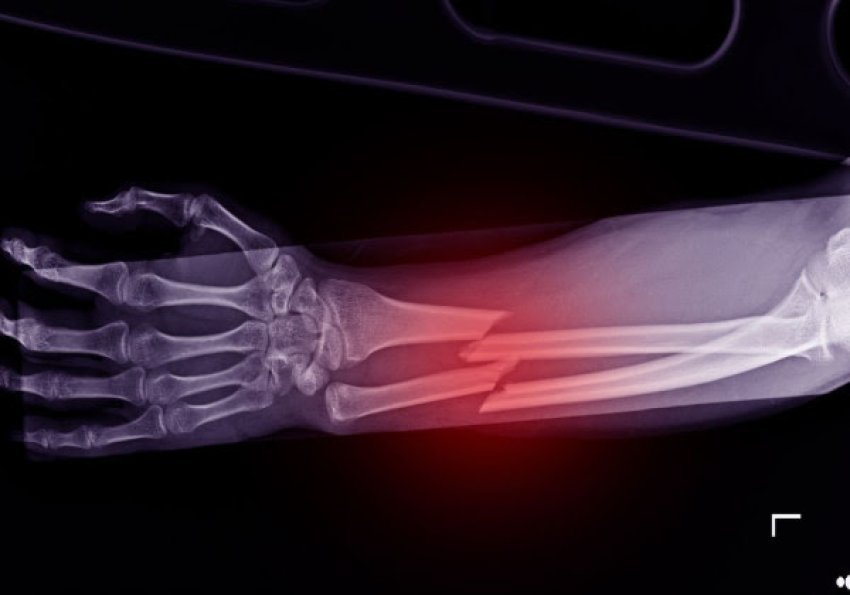

​Shpiket ngjitësi i kockave, që riparon frakturat për tri minuta

Shkencëtarët kinezë kanë zhvilluar një ngjitës kockash të ri të quajtur ”Bone-02”, që është i aftë të riparojë frakturat në vetëm tri minuta me një injeksion të vetëm, i frymëzuar nga mënyra se si ngjiten ostriket në kushte lagështie, shkruan italianstonic.it.

Sipas raportimeve të medias, produkti është testuar tashmë në mbi 150 pacientë.

Ai siguron një lidhje shumë të fortë dhe tretet ndërsa kocka shërohet duke shmangur kështu përdorimin e pllakave metalike ose vidave.

Megjithatë, rezultatet janë ende paraprake, pasi ka mungesë të botimeve shkencore të rishikuara nga kolegët, pak informacion mbi sigurinë afatgjatë dhe asnjë verifikim të pavarur.

Prandaj, ekspertët kërkojnë kujdes duke theksuar se efektiviteti i tij mund të konfirmohet vetëm nga prova klinike më të shumta.